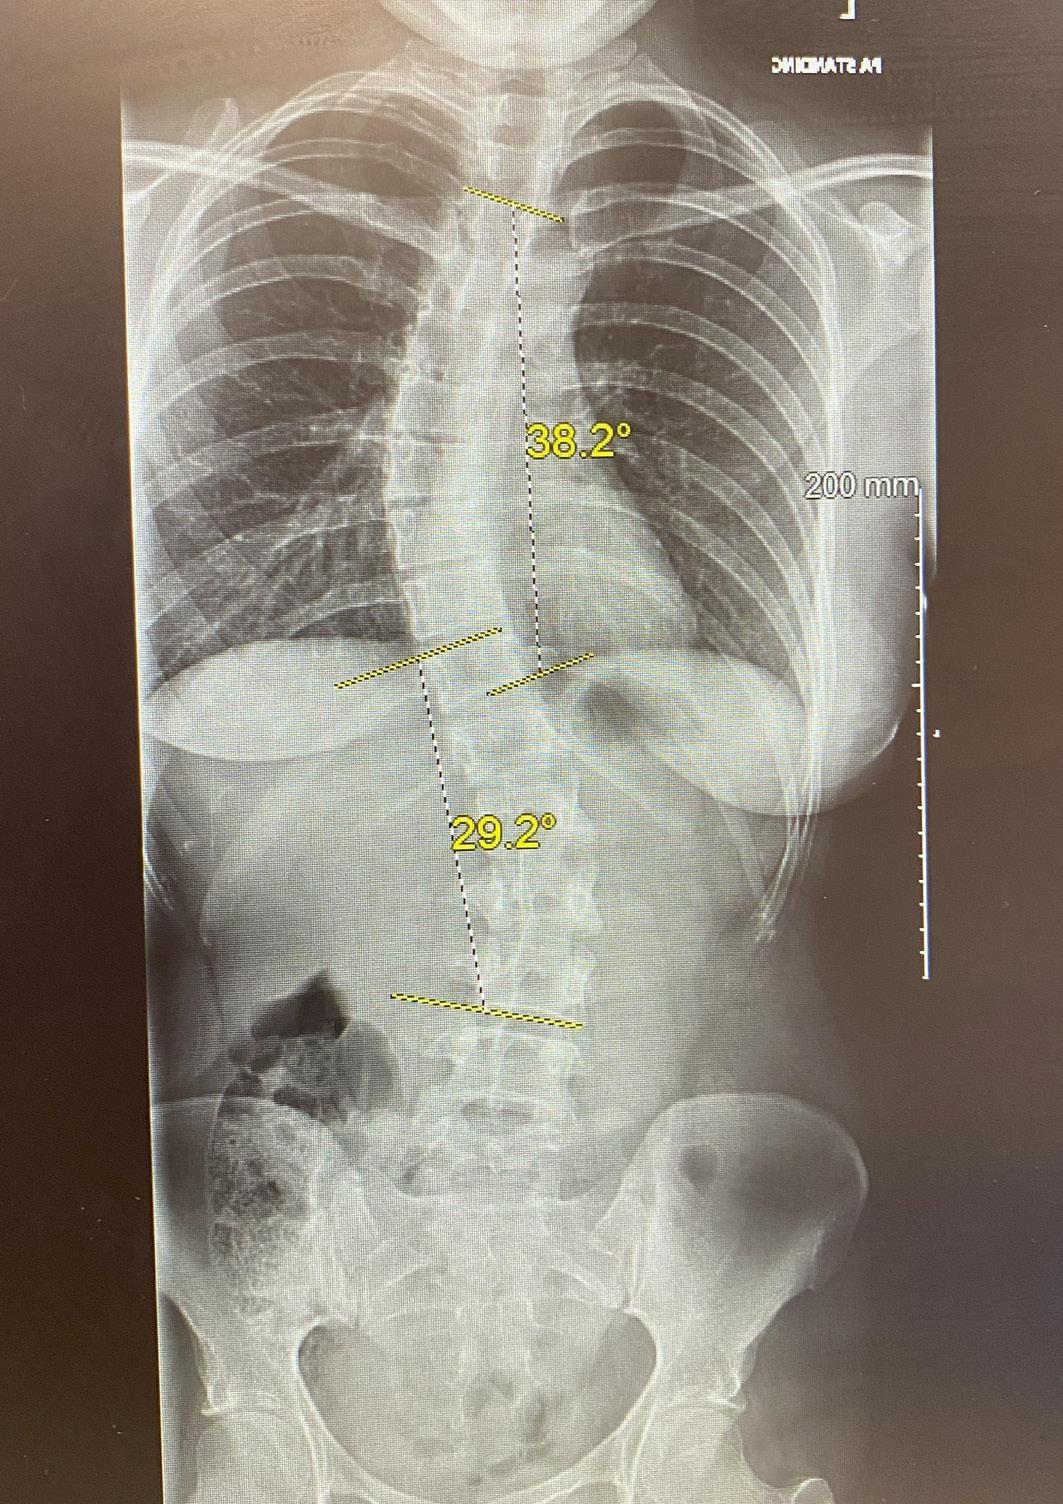

By the end of 2020, I had another X-ray and a virtual consultation with a different specialist. To my shock, my scoliosis had worsened—my thoracic curve had increased to 40 degrees, and my lumbar curve had reached 30 degrees. I was now on the threshold for major spinal fusion surgery. The consultant didn’t seem to understand why I was so upset, but mentally, I knew I couldn’t go through with surgery. After making this clear, he finally mentioned another option—scoliosisspecific physiotherapy. Why he didn’t start with this, I’ll never know!